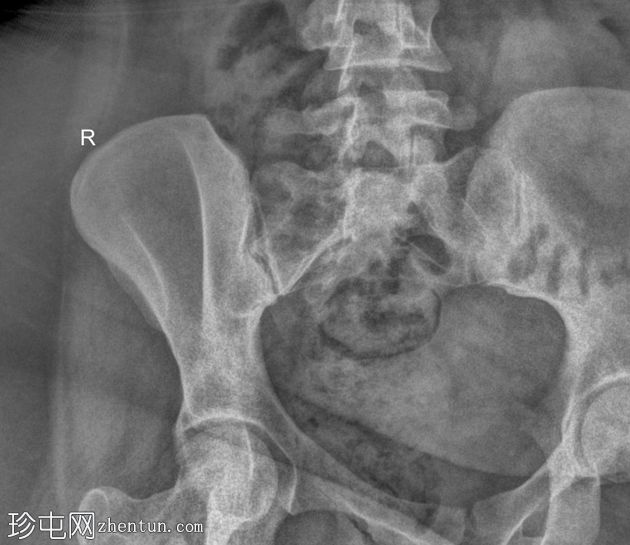

正位

骶髂关节正位和斜位X线片显示正常。